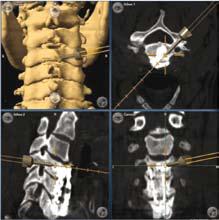

■利用電腦導航技術幫病人進行翻修手術,再做後路神經減壓,並且精確地利用椎弓根螺絲去固定他的頸椎,紓緩他的痛楚。